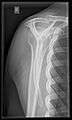

- Y-projection

The lateral contour of the shoulder should be positioned in front of the film in a way that the longitudinal axis of the scapula continues parallel to the path of the rays. This method reveals:[19]

- The horizontal centralization of the humerus head and socket.

- The osseous margins of the coraco-acromial arch and hence the supraspinatus outlet canal.

- The shape of the acromion

This projection has a low tolerance for errors and accordingly needs proper execution.[19] The Y-projection can be traced back to Wijnblath’s 1933 published cavitas-en-face projection.[20]

Y-projection conventional radiography